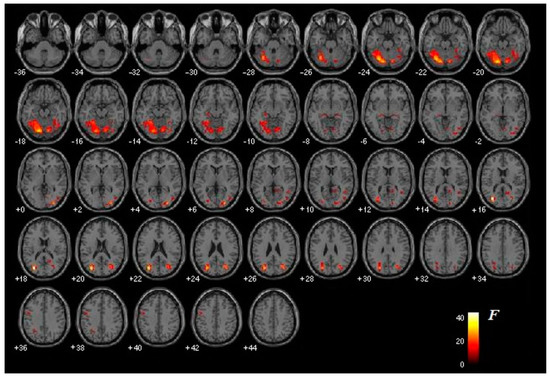

3.2. Functional Brain Activation